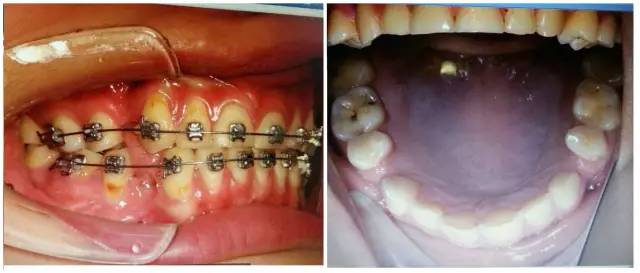

病例:患者,女,22歲。

主訴:8年前曾行正畸矯正,現(xiàn)因美觀及功能需求,要求重新矯治。

現(xiàn)病史:2個(gè)月前,開始戴用矯治器,以0.012Niti初始絲,近2個(gè)月來無明顯不適。2天前,上前牙開始出現(xiàn)咬硬物疼痛,冷熱刺激痛,自覺松動(dòng)。

檢查:上前牙松(Ⅱ)°,牙齦紅腫,牙周膜間隙增寬。(如照片所示)

口內(nèi)情況,如以下照片所示: